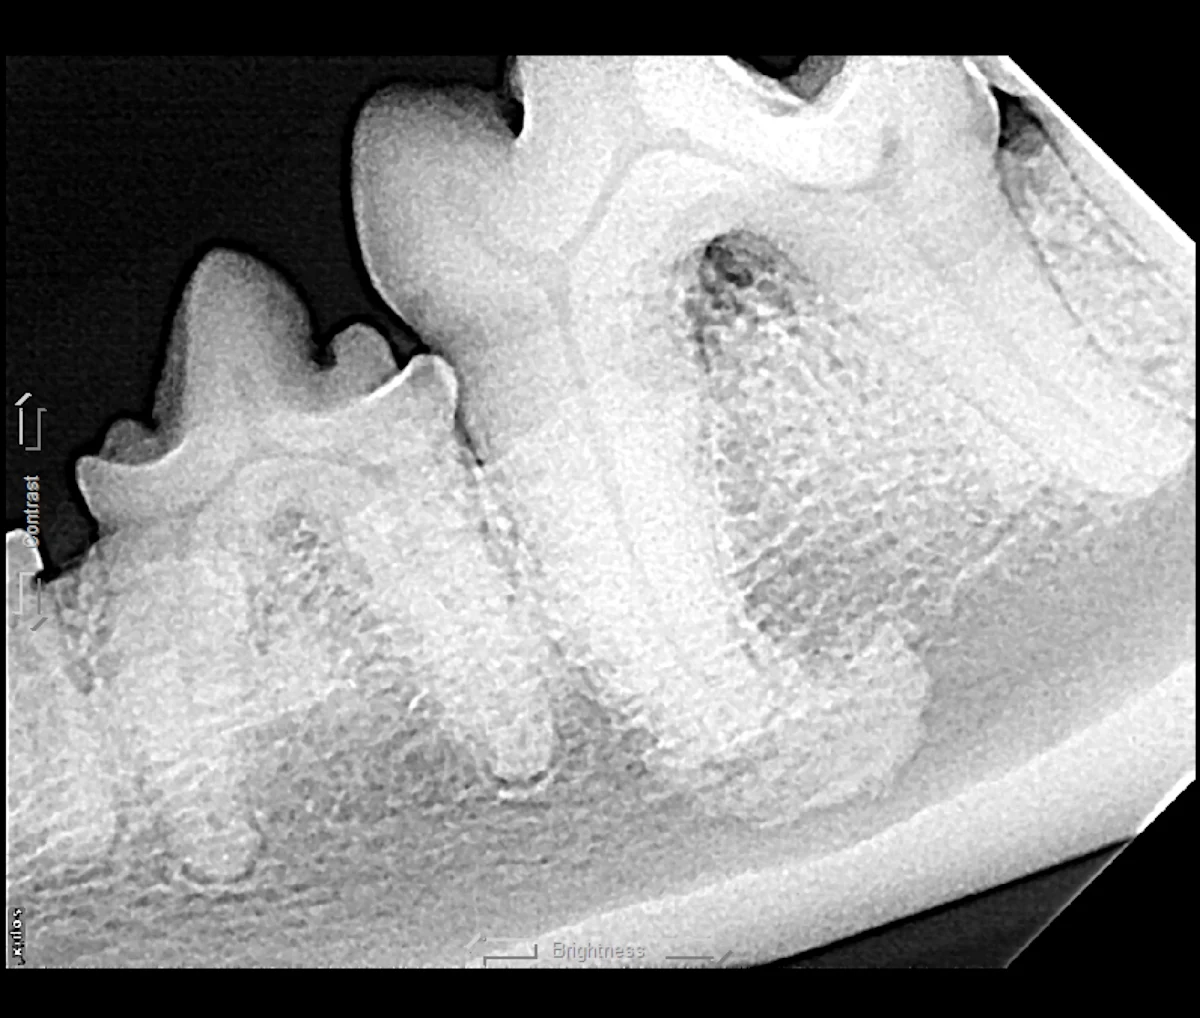

Root ankylosis, root resorption, root dilaceration (ie, curvature), and/or bulbous roots can increase the difficulty of a tooth extraction (Figure 12). Tooth roots occasionally break during extraction attempts. Diseased tooth roots should typically not be left in place due to the potential for pain and infection.5 Safe root extraction includes removal of additional alveolar bone or widening of the alveolus with a high-speed bur to create a moat around the remaining root fragment prior to lifting it out (see Suggested Reading).5

Root ankylosis (A), root resorption (B), bulbous root (C; arrow), and root dilaceration (ie, curvature) (D; arrow) are tooth root anomalies that can increase the difficulty of tooth extraction.

Root tips may be easily displaced into the mandibular canal or the nasal passage and maxillary sinus. Displacement is more likely with significant oral disease or bone loss around the root apex. Roots displaced into abnormal locations should be removed surgically by a board-certified veterinary dentist.